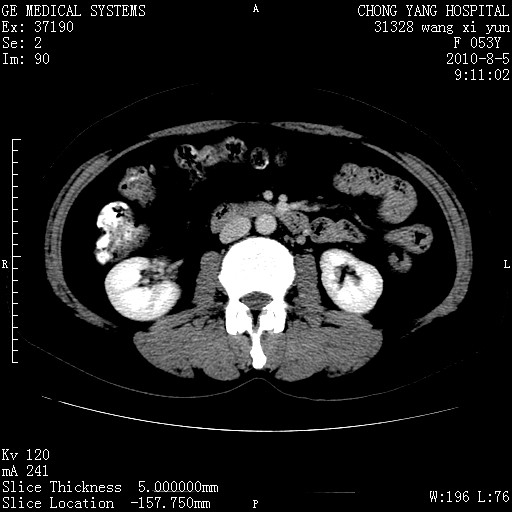

标题: CT28214:F41Y 血尿二十天,建议盆腔平扫加增强。

1)考虑肝左叶胆管细胞癌。2)脂肪肝。